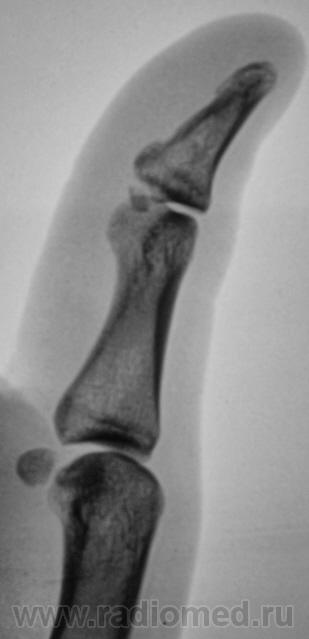

Пол пациента: Мужской пол Тип патологии: Травма Область исследования: Скелетно-мышечная система Методы исследования: Rg Что это? Отколовшийся фрагмент или чсто-то другое? Травма была накануне. Обратился к хирургу поликлиники, направлен хирургом на рентгенографию. https://radiomed.ru/sites/default/files/styles/case_slider_image/public/user/12/2.P5200014.JPG?itok=kSaxtyoS https://radiomed.ru/sites/default/files/styles/case_slider_image/public/user/12/3.P5200014a.jpg?itok=XP5p8ESI https://radiomed.ru/sites/default/files/styles/case_slider_image/public/user/12/4.P5200014v.jpg?itok=CE-t0-Id https://radiomed.ru/sites/default/files/styles/case_slider_image/public/user/12/5.P5200014vu.jpg?itok=D6GOyUSZ ID:3946 Thu, 20/05/2010 - 20:38 #1 Ola-la Offline Last seen: 10 months 3 weeks ago Joined: 06.12.2008 - 09:33 Posts: 1786 Это перелом. https://www.instagram.com/pediatricradiology/ Thu, 20/05/2010 - 20:49 #2 Анатолий Владим... Offline Last seen: 7 years 10 months ago Joined: 16.10.2009 - 21:16 Posts: 1941 Есть перелом... Thu, 20/05/2010 - 23:14 #3 Илья Васильевич... Offline Last seen: 13 years 11 months ago Joined: 25.04.2010 - 14:23 Posts: 89 перелом. телу- мера, душе-Вера

Это перелом.

Есть перелом...